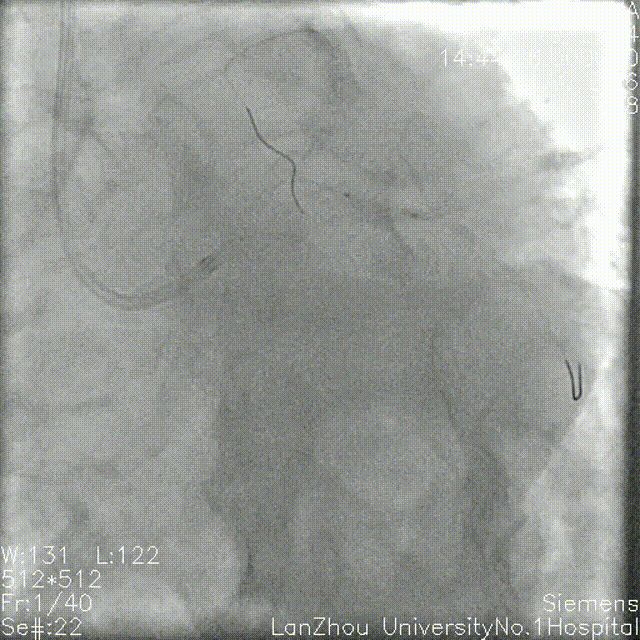

右冠造影:

全程斑块伴有钙化;

第二弯可见支架影,支架未见明显再狭窄。

第二弯可见支架影,支架未见明显再狭窄

右冠可暂不处理。

A. 右冠全程钙化,支架贴壁良好,不做特殊处理;